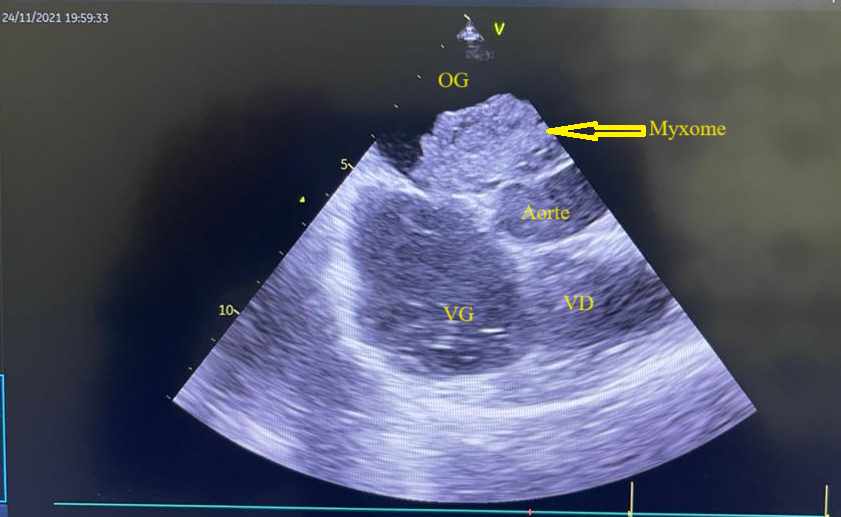

L’électrocardiogramme s’inscrivait en rythme sinusal régulier avec une fréquence cardiaque à 74bpm. L’échocardiographie transthoracique a mis en évidence une volumineuse masse intra-atriale gauche mesurant 57mm x 42mm appendue au septum inter atrial, avec dilatation de l’oreillette gauche et de l’anneau mitral associée à une insuffisance mitrale sévère grade 4/4. Le diagnostic retenu était un probable myxome de l’oreillette gauche compliqué d’insuffisance mitrale sévère. Les caractéristiques de cette masse ont été confirmées à l’échographie cardiaque transœsophagienne (figure 1). La fonction systolique du ventricule gauche était préservée avec une dysfonction diastolique grade 2. Les pressions de remplissage du ventricule gauche étaient normales. Le bilan biologique n’avait noté aucune anomalie.

Figure 1 : Echocardiographie transoesophagienne en bi dimensionnelle incidence bicave montrant un myxome de l’oreillette gauche appendu au septum inter atrial (Cas clinique n°1). OG= oreillette gauche ; OD= oreillette droite